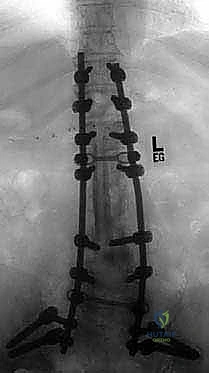

عملية دمج الفقرات (Spinal Fusion) هي إجراء جراحي يهدف إلى ربط فقرتين أو أكثر بشكل دائم، مما يزيل الحركة غير الطبيعية والمؤلمة بينهما، ويعيد الاستقرار الميكانيكي إلى العمود الفقري. في حالتنا هذه، يتم التركيز بشكل خاص على المنطقة الصدرية القطنية (Thoracolumbar Junction)، وهي المنطقة الانتقالية الحرجة التي تربط الجزء العلوي من الظهر (القفص الصدري الصلب) بالجزء السفلي (المنطقة القطنية المتحركة). يتم التثبيت باستخدام أدوات طبية معدنية متطورة (Instrumentation) مثل المسامير السويقية (Pedicle Screws) والقضبان المصنوعة من التيتانيوم.

السويقات الفقارية (Pedicles): دعامة التثبيت الأساسية والمحورية

تعتبر السويقة الفقارية (Pedicle) جسرًا عظميًا أسطوانيًا يربط الأجزاء الخلفية للفقرة (القوس الفقري) بالجسم الفقري الأمامي الضخم. في جراحة دمج الفقرات الحديثة، تعتبر السويقة نقطة التثبيت الرئيسية والأقوى للمسامير المستخدمة في العملية (Pedicle Screws). يختلف شكل وحجم وزاوية السويقات بشكل كبير على طول العمود الفقري، وفهم هذه الفروق الدقيقة أمر بالغ الأهمية للجراح لضمان وضع المسامير بأمان تام وفعالية قصوى دون الإضرار بالأعصاب أو الأوعية الدموية.

1. السويقات الصدرية (T1-T12):

2. السويقات القطنية (L1-L5):

3. السويقات العجزية (S1):

* الحجم: سويقة الفقرة العجزية الأولى (S1) هي الأوسع والأضخم بين جميع السويقات، مما يوفر نقطة تثبيت قوية جداً لقاعدة البناء الجراحي.

- تبني أحدث التقنيات التكنولوجية: يستخدم د. هطيف تقنيات الجراحة الميكروسكوبية الدقيقة (Microsurgery)، ومناظير المفاصل بدقة 4K، وأنظمة الملاحة الجراحية لضمان وضع المسامير بدقة متناهية (Sub-millimeter accuracy) وتجنب أي إصابة للأعصاب.